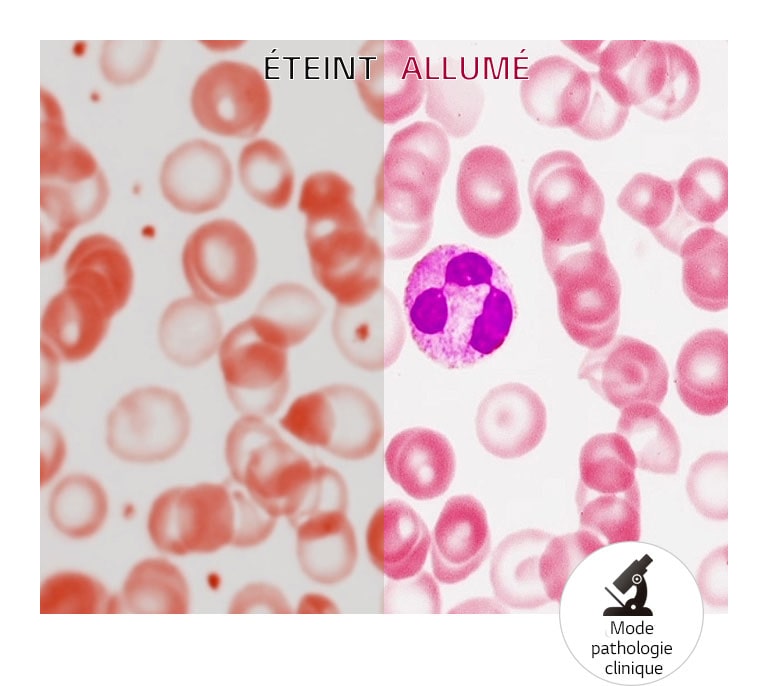

- Mode pathologie clinique

Mode Pathologie

OUI